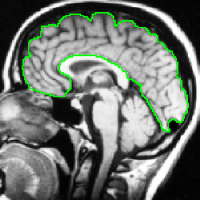

4.1 Metrication artifacts and minimal surfaces

We begin by comparing the CCMF segmentation result with the classical max-flow algorithm (graph cuts). Figure 3 shows the segmentation of a brain, in which the contours obtained by graph cuts are noticeably blocky in the areas of weak gradient, while the contours obtained by both AT-CMF and CCMF are smooth.